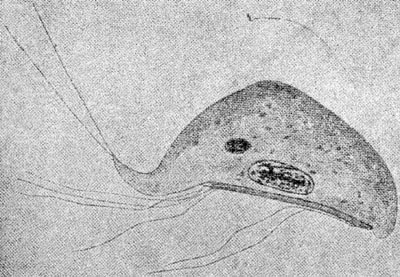

Fig. 4.—Death-cup; destroying angel (Amanita phalloides Fries); reduced; natural size: cap, 31/2 inches; stem, 71/2 inches. (After Marshall, The Mushroom Book, by courtesy of Doubleday, Page & Company.)

The character of the poison was first carefully investigated by Kobert, who showed that the Amanita extract has the power of laking or dissolving out the coloring matter from red blood corpuscles. This hemolytic action is so powerful that it is exerted upon the red cells of ox blood even in a dilution of 1:125,000. Ford[26] has since shown that in addition to the hemolytic substance another substance much more toxic is present in this species of Amanita and he concludes that the poisonous effect of the fungus is primarily due to the latter ("Amanita toxin"). The juice of the cooked Amanita is devoid of hemolytic power, but is poisonous for animals in small doses, a fact that agrees with the observation that these mushrooms, after cooking, remain intensely poisonous for man. Extensive fatty degeneration in liver, kidney, and heart muscle is produced by the true Amanita toxin. In the Baltimore [p.24] cases studied by Clark, Marshall, and Rowntree[27] the kidney rather than the liver was the seat of the most interesting functional changes. These authors conclude that the nervous and mental symptoms, instead of being due to some peculiar "neurotoxin," are probably uremic in character. No successful method of treatment is known. An antibody for the hemolysin has been produced, but an antitoxin for the other poisonous substance seems to be formed in very small amount. Attempts to immunize small animals with Amanita toxin succeed only to a limited degree.[28]